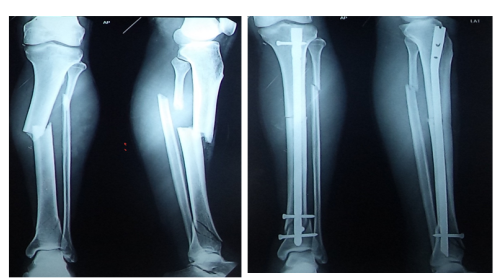

We have got 206 bones in our body. Each bone is strong and compact but they can withstand only a particular amount of weight and force. If the weight and force exceed the capacity of that particular bone then the bone will bend and get fractured. If the fractured fragments are very near to each other they unite very easily. This kind of fractures can be treated without surgery by the use of plaster of Paris. Like that the hairline fractures can be immobilised for a few weeks so that the fracture will unite on its own.

More